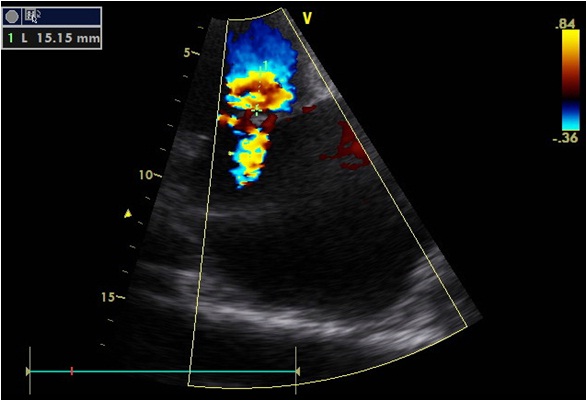

Echocardiographic signs for a flail mitral valve leaflet. This was a retrospective evaluation of 54 patients who had (1) significant and sensitivity is maximized when they are combined. (J AM Soc ECHO 1988;1:433-45.) . Mitral valve regurgitation is a common clinical problem with ... Document Viewer

Statistical Comparison of M Mode and Two Dimensional Echocardiographic Diagnosis of Flail Mitral Leaflets GARY S. MINT& MD (Group I) had a flail mitral valve leaflet, and 19 patients (Group II) had intact chordae tendineae. niques in the diagnosis of a flail mitral leaflet. ... Document Viewer

Myxomatous Mitral Valve Flail Middle Scallop Posterior Leaflet CP1045315-2 Sudden Death in Mitral Regurgitation due to Flail Leaflet •384 pt with flail mitral leaflet diagnosed by Echo (1980-1994) ... View Document